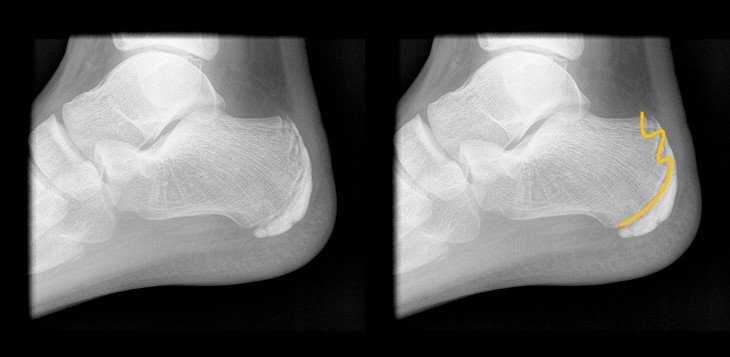

세버씨병의 경우 방사선 촬영을 통해 확인할 수 있다. 활동량이 많은 아이가 뒤꿈치 통증을 호소한다면 방사선 촬영으로 확인해 볼 수 있다. 방사선 촬영을 해보면 울퉁불퉁한 성장판이 관찰되기도 한다. 부드러운 형태보다 아킬레스 힘줄에 의해 당김이 발생할 때 불편함을 더 느낄 수 있다.